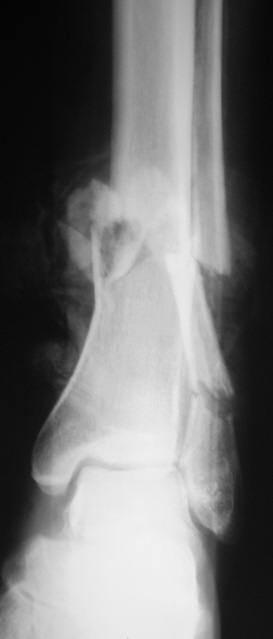

Травма. Произведена рентгенография в стандартных проекциях.

Тип: Клиническое наблюдение

Область: Скелетно-мышечная система

Модальность: Rg

Дата: 17.05.2010 - 18:15